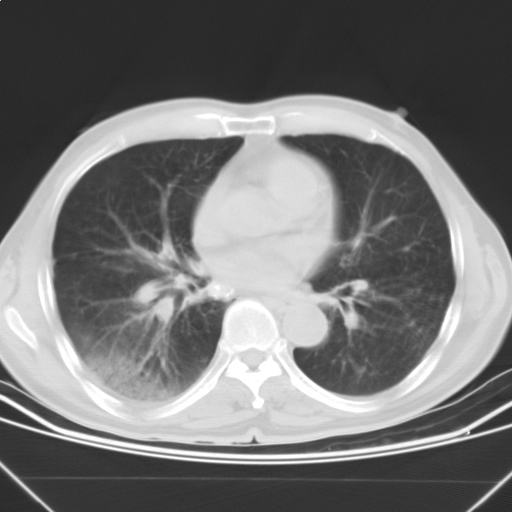

以下是引用随光逐影在2009-5-1 13:53:00的发言:[br]考虑为:1)两肺血行播散型肺结核;2)右肺下叶炎症感染。3)右侧胸膜增厚。